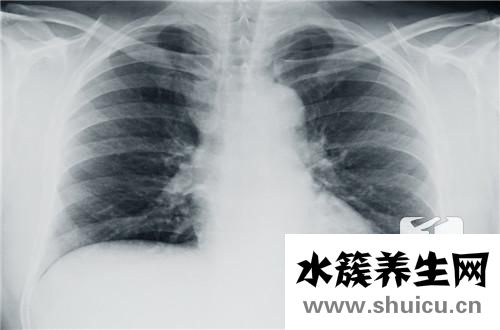

有的人覺得自己的胸在什么都沒有的情況下突然悶了原因?這需要考慮原因,可能是環境因素造成的,因為空氣污染導致呼吸道受到影響;或者是因為心臟病的癥狀,這種情況需要老年人高度重視。自然,胸口還有一些...